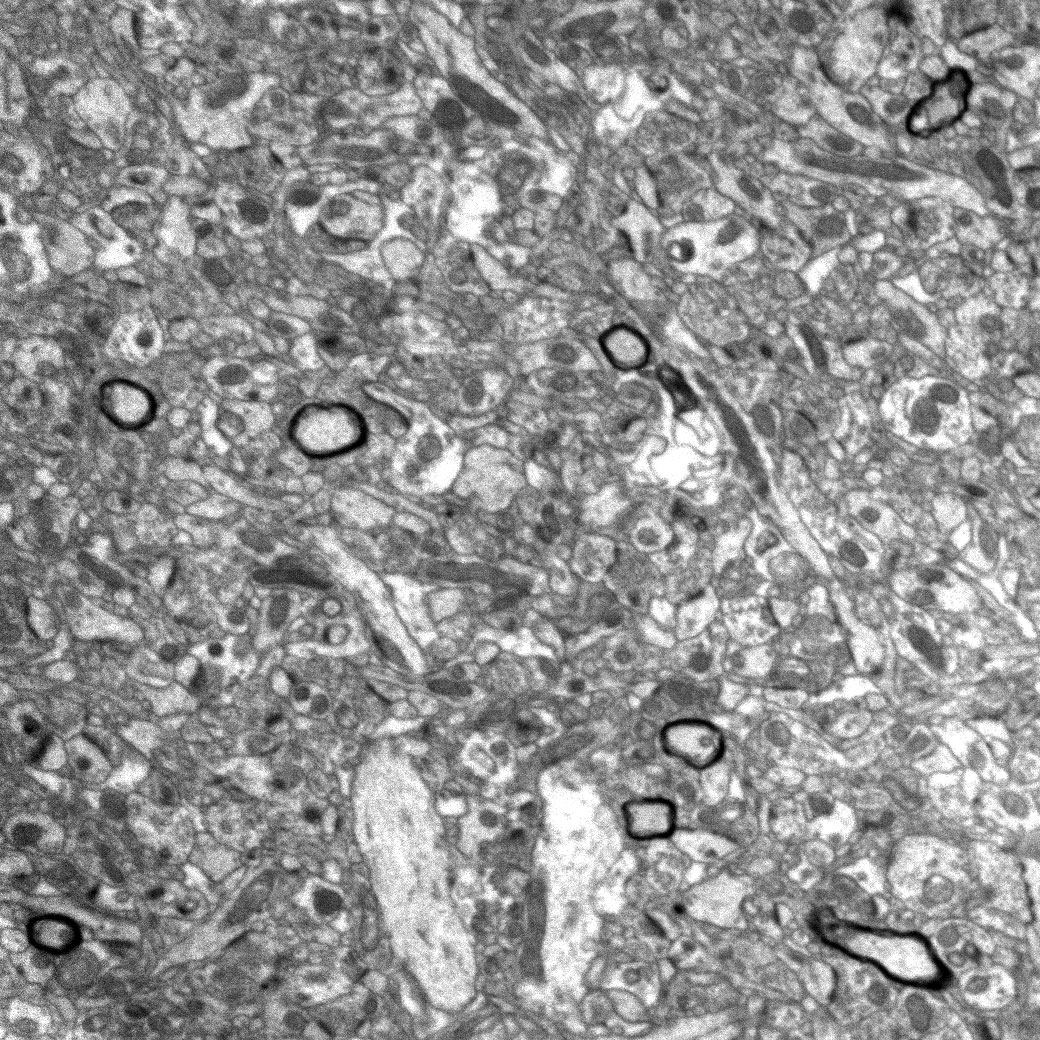

Image

EM of myelinated axons in control mouse

EM of myelinated axons in conditioned mouse

High-resolution electron microscope images show increased number of myelinated axons (dark circles) in the medial prefrontal cortex of mice that experienced fear learning (right) compared to normal mice (left). Image credit: Chan & Kheirbek labs